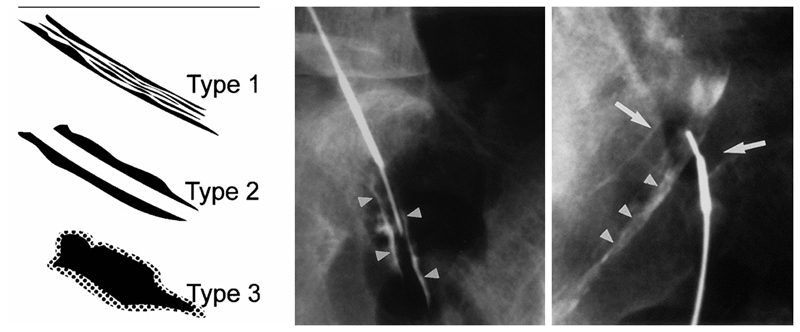

RN入路注射又可分为两种方式,即神经根鞘膜内注射(intra-epineuralinjection)和神经根周围注射(intra-epineuralinjection)。通过造影剂注射可以区分这两种不同的方法,当针尖进入神经根鞘膜内时,会获得神经根内羽毛状神经纤维的显影,而针尖在神经根周围时,造影剂会显示神经根的轮廓。

图4

Pfirrman等对比RN入路两种注射方法的效果认为,尽管两种方法治疗结果相似,但神经根鞘内注射往往会给患者带来严重疼痛,这种注射所带来的疼痛往往已经超出疾病本身的疼痛,因此,神经根鞘内注射是完全没有必要的。